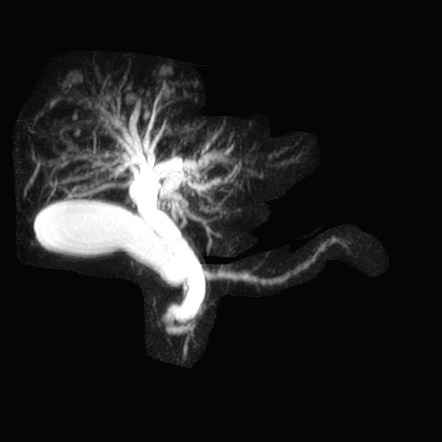

Caroli disease (todani type V) plus ADPKD

Caroli’s is associated with medullary sponge kidney and ADPKD and ARPKD

caroli disease (todani type V)

mesh of small bile ducts in the liver parenchyma draining into gallbladder